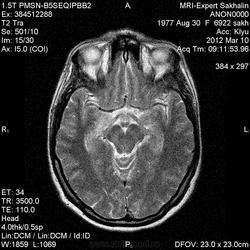

Направительный диагноз:головная боль напряжения.

Краткий анамнез заболевания, жалобы: головные боли,снижение памяти, раздражительность, снижение аппетита в течение 3-х месяцев.

Подозреваю демиелинизацию,гиппокампальный склерз ( тогда базальные ядра и ножки при чем?),ишемические проявления -не знаю!Помогите , пожалуйста, начинающему доктору!

Лимбический энцефалит? Паранеопластический процесс? А где диффузионные программы- не помешают. Нужно подумать (или спросить у ннемо, например))).

Написала дифф.ряд: лимбический энцефалит, лимфому ЦНС, герпетический энцефалит.

С лимфомой верифицированной не встречался, картина не противоречит паранеопластическому или герпетическому энцефалиту. Склероз гиппокампов: нет уменьшения их размеров, зоны изменений сигналов гиппокампами не ограничиваются, есть кроме височных долей и в ножках мозга, опять же накопление контраста.

Женщина 1977 года рождения.Со слов мужа , около 3/х мес. назад начались головные боли, снижение памяти, раздражительность снижение аппетита.Перенесла какую-то инфекцию типа ОРЗ.С ней разговаривать трудно-мало что помнит.На асоциальную , наркоманку не похожа-приличная с виду женщина.Неврологический статус хотела выяснить у лечащего врача по телефону, но она живет в районе,и телефон не указала .Визуально-неврологический статус без особенностей.В направлении-головная боль напряжения .Нет указаний -на что обратить внимание.

Уважаемые коллеги! Поясните пожалуйста, данные за энцефалит вы где видите? Это повышение сигнала на Т2 на участках или другие изменения. Не большой спец, поэтому интересуюсь для опыта

Ишемические изменения и темпоральный склероз - нет.

Для И.Бондаренко - вы все правильно указали - гипер- в Т2W, а также гипо- в Т1W, + очаги накопления контраста

В данном случае больше данных за воспалительный энцефалит - есть синусит (не нравиться гиперинтенсивное включение парацентрально в пазухе -грибок????) .

С учетом накопления контраста да и по локализации однозначно не опухоль, не инсульт, не травма. Из классики да действительно герпес любит виски, также и иные вирусные могут быть (этиологию иной раз не угадаешь - бессмыслено), может быть и тбс. но сос четов не сбрасывал бы паранеопластический - тем более женщина да и контраст накопила как бы не молочка?? Ну и совсем чтоб запутать нет ли В20? только на внешний вид и на мужа не надо ориентироваться - у нас и у врачей и у студентов мед вузов бывает - пройденный этап(((